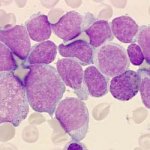

ЛимфогранулематозЛимфогранулематоз — тяжелое общее заболевание, протекающее с опухолевидными разрастаниями лимфатических... ЛимфогранулематозЛимфогранулематоз — тяжелое общее заболевание, протекающее с опухолевидными разрастаниями лимфатических...